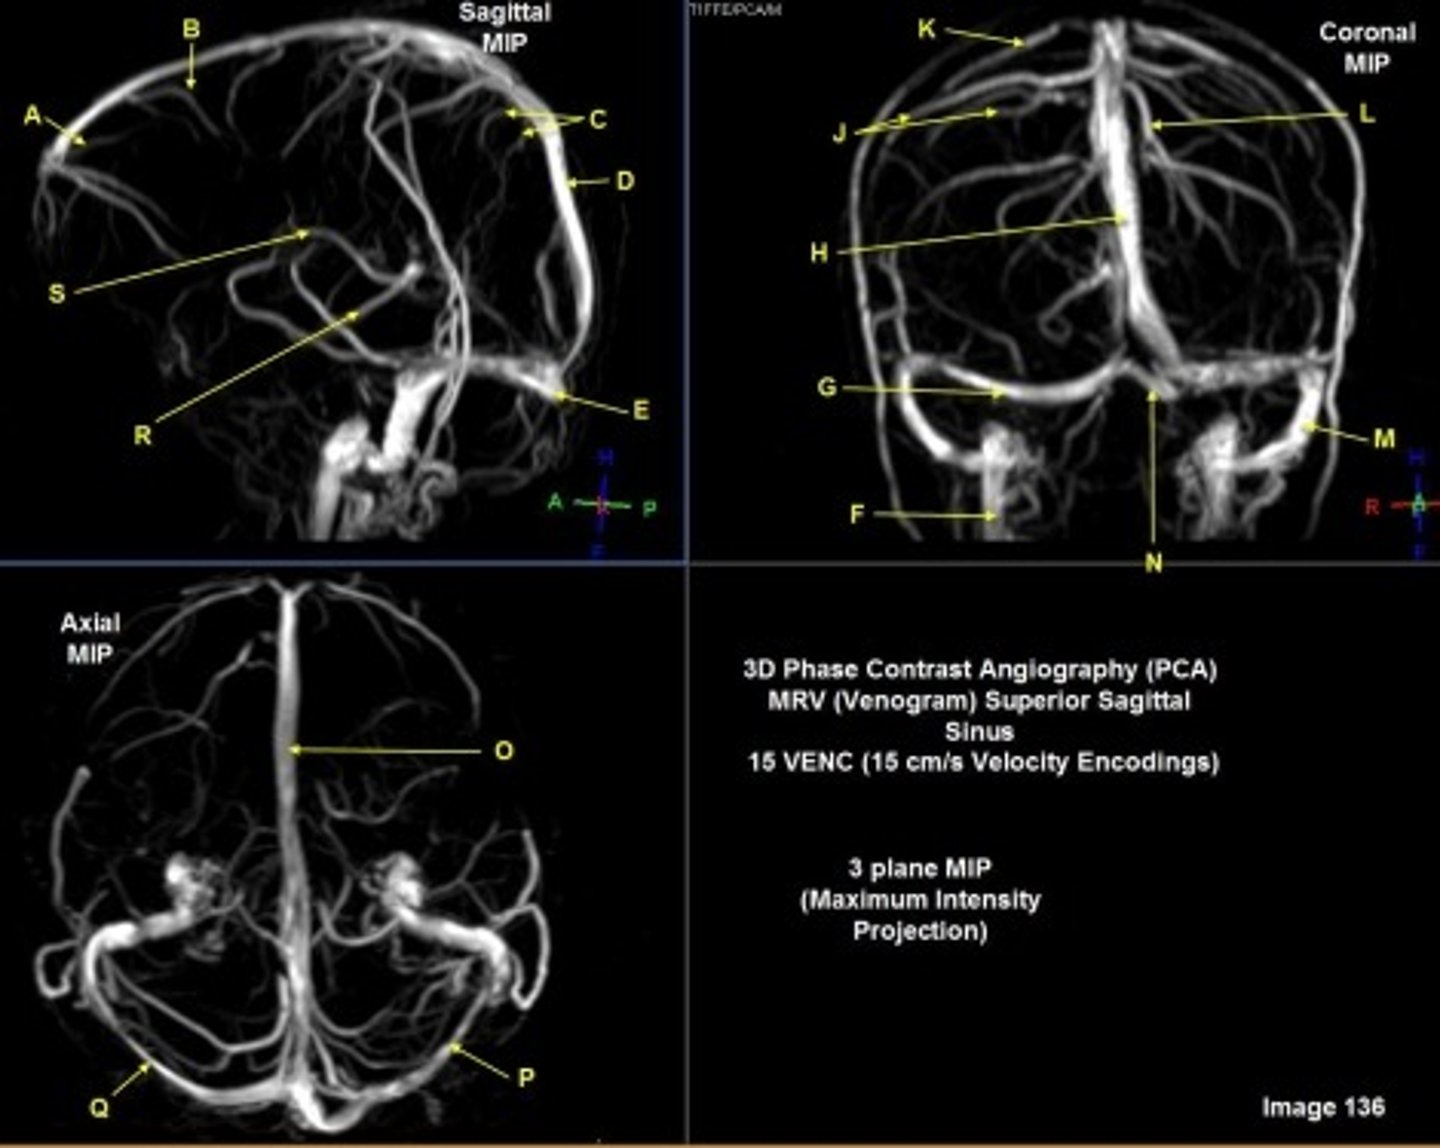

B

posterior frontal vein

C

parietal veins

D

superior sagittal sinus

E

Torcular herophili

F

internal jugular vein

G

R transverse sinus

H

J

R parietal veins

L

L parietal veins

K

Vein of trolard (superior anastomotic vein)

M

Left sigmoid sinus

N

O

P

Left transverse sinus

S

Internal cerebral vein

A

anterior frontal vein

right transverse sinus

left parietal veins

Vein of Trolard